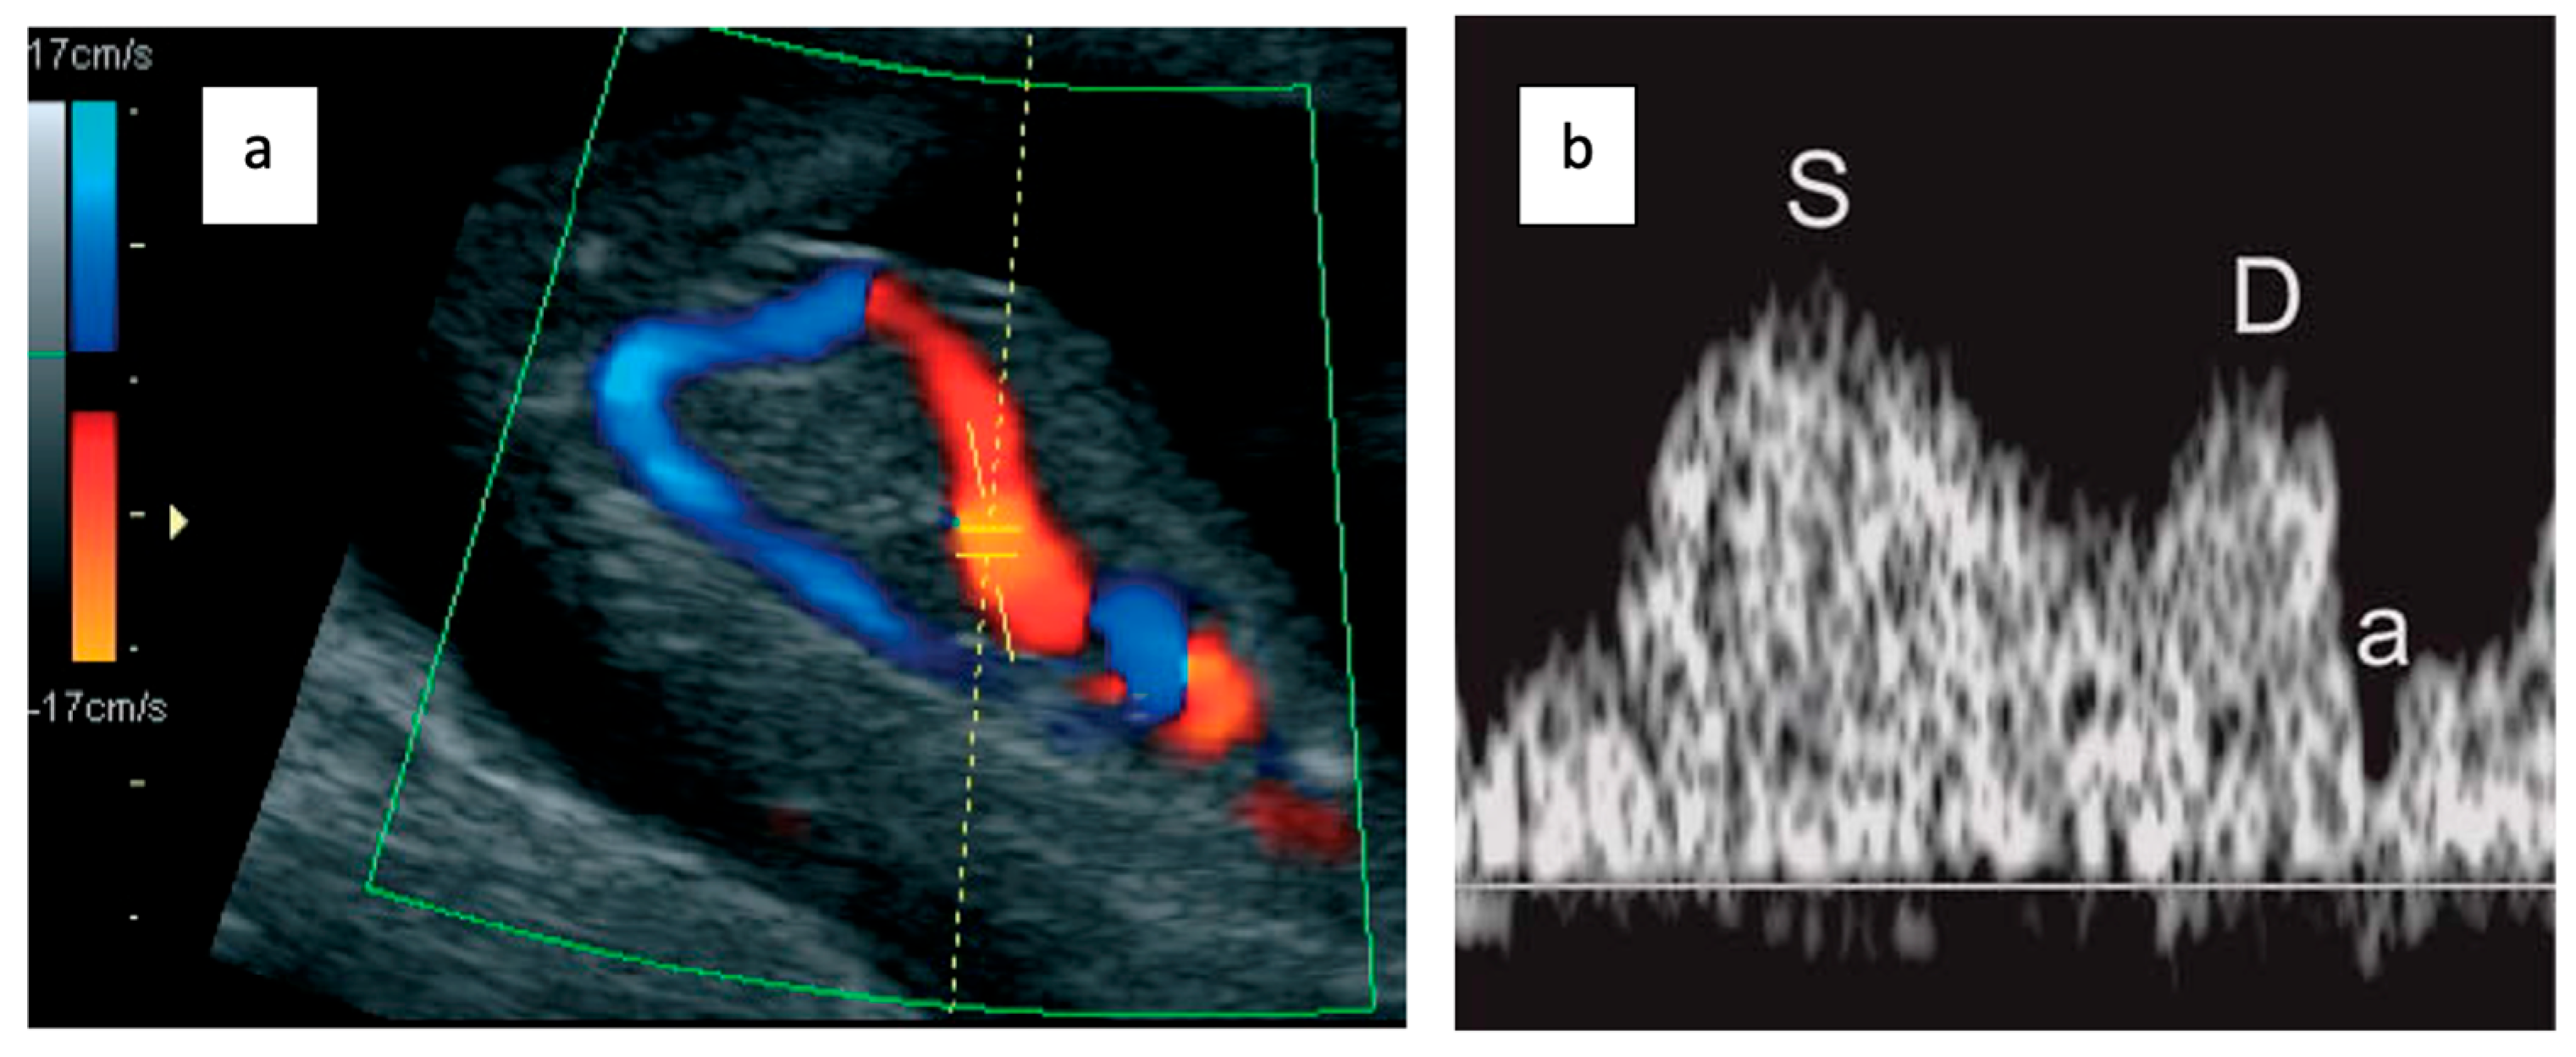

- Right ventral mid-sagittal view with color flow mapping showing the umbilical vein, DV, and heart.

- Small pulsed Doppler sample volume (0.5–1.0 mm) positioned in the aliasing area above the umbilical sinus.

- Insonation angle < 30°.

- Low filter setting (50–70 Hz).

- High sweep speed (2–3 cm/s) for waveform analysis.

- Qualitative assessment of the a-wave (positive, absent, or reversed).

- Manual tracing for DV pulsatility index (PIV) measurement.